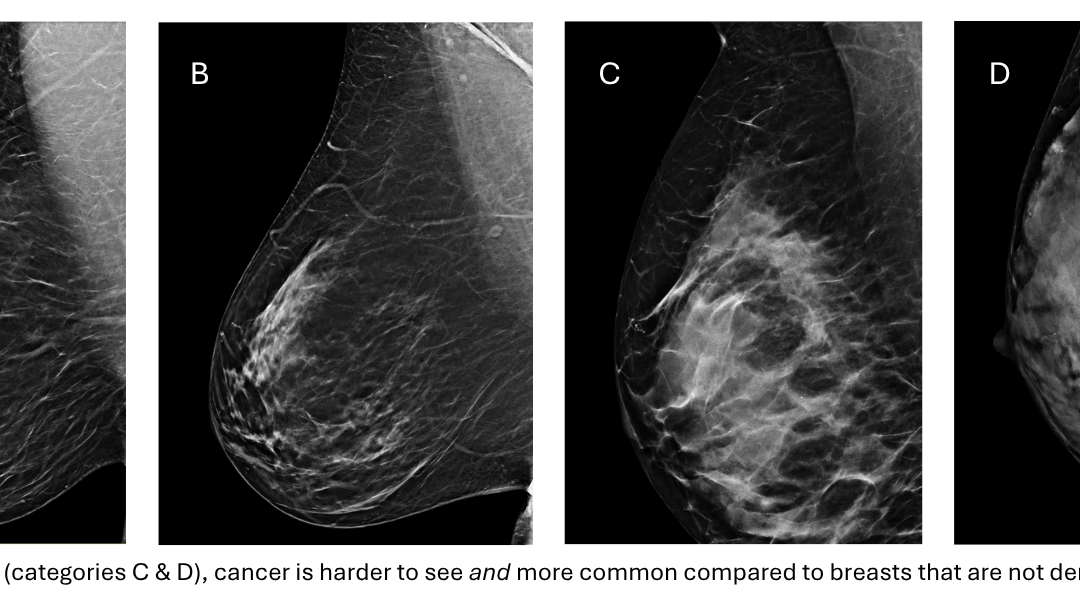

Instead, we are assessing how much of the breast is made of fat (transparent on the mammogram) versus gland (white clouds on the mammogram). Breasts come on a spectrum, from completely clear to completely cloudy, that we divide into four categories (A-D).

completely clear to completely cloudy that we divide into four categories (A-D).